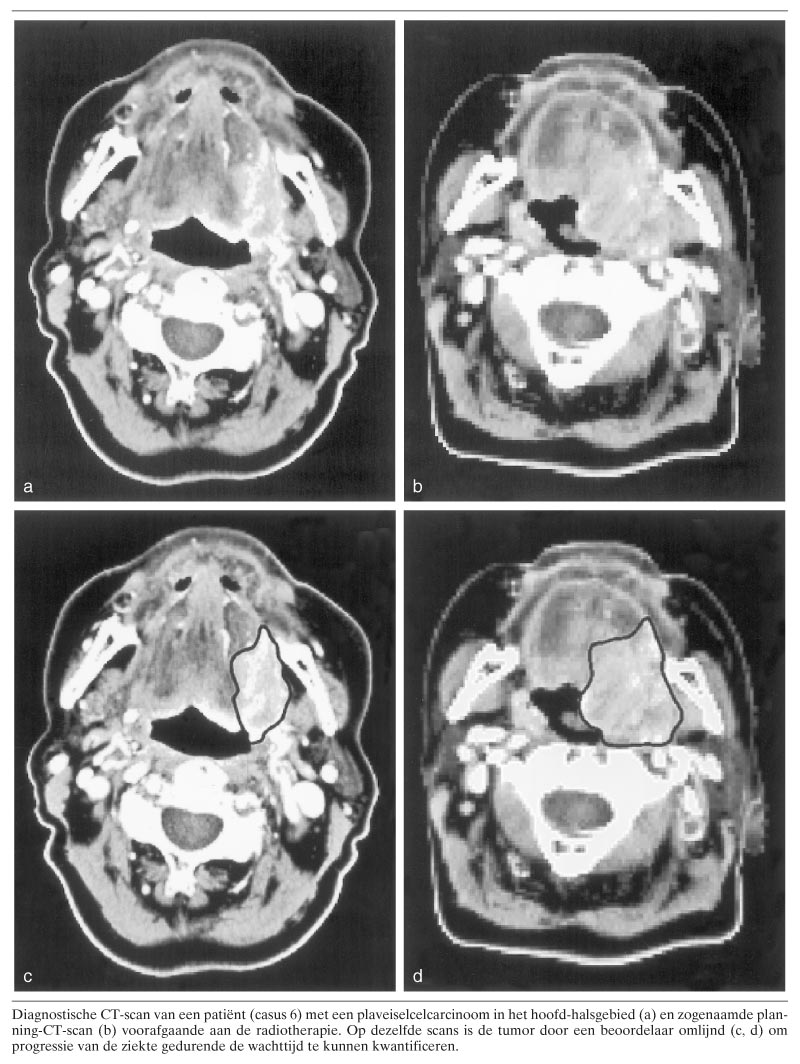

Tabel 2 toont de absolute en procentuele veranderingen van het tumorvolume als gemiddelde van 3 waarnemingen. Bij 1 klier vond groei van meer dan 100 plaats; deze werd daarom ook opgenomen in tabel 2. Op basis van de toename van het tumorvolume waren 3 groepen te onderscheiden (zie tabel 2): in de eerste groep (n = 4) was geen evidente groei waarneembaar. De tumorvolumeverandering bedroeg minder dan 25. In de tweede groep (n = 5) was er groei tussen 25 en 100. In één geval (casus 12) was er een minimale lokale tumorvolumeverandering, maar werd, op basis van de fors toegenomen omvang van een klier, de patiënt in deze groep geplaatst. In de derde groep (n = 4) werd groei vastgesteld van gemiddeld meer dan 100 van het oorspronkelijke volume. De figuur illustreert de duidelijk waarneembare groei in casus 6.